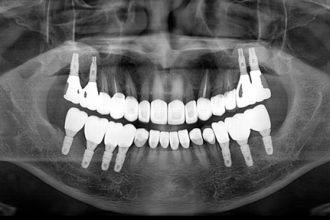

임플란트